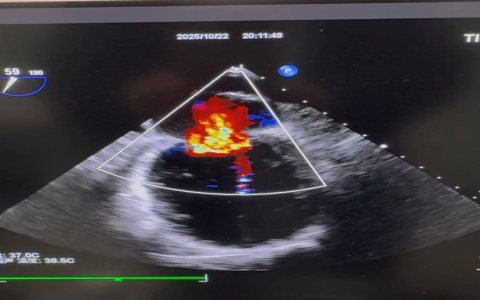

從此,他的生活被徹底改變——“快走、飽餐時出現(xiàn)氣短,不能平臥”成為常態(tài),活動能力斷崖式下降。他輾轉(zhuǎn)多家醫(yī)院,服用了包括沙庫巴曲纈沙坦、比索洛爾、維利西呱在內(nèi)的多種抗心衰藥物,但病情依然反復(fù)發(fā)作,多次因“急性心力衰竭”入院。僅僅在一周前,門診檢查再次拉響警報:心臟超聲顯示左心室顯著擴大,收縮功能嚴(yán)重減低(射血分?jǐn)?shù)EF值低至33%,僅為常人的一半),更致命的是,出現(xiàn)了大量的二尖瓣反流(反流面積達(dá)9.8cm2)和重度肺動脈高壓。

超聲提示:后葉栓系二尖瓣大量偏心型返流

這顆心臟,就像一個疲憊不堪、閥門失靈的水泵,無法將血液有效泵出,導(dǎo)致血液大量倒流,陷入惡性循環(huán)。對于左先生這樣心功能極差的嚴(yán)重心衰患者,傳統(tǒng)外科開胸手術(shù)修復(fù)瓣膜的風(fēng)險極高,幾乎被視為“禁區(qū)”。